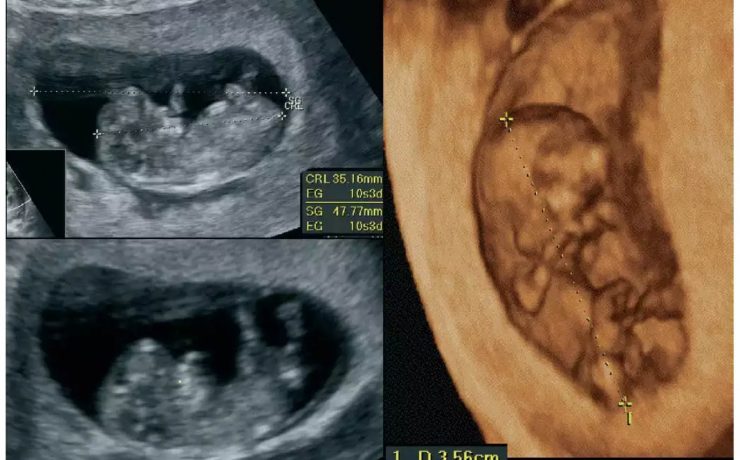

Síndrome de rokitansky y fibroma pélvico

El síndrome de Rokitansky, es la anomalía más grave del tracto reproductivo femenino. Consiste en la ausencia congénita de vagina y útero ausente o rudimentario, como consecuencia de la falla en el desarrollo Mûlleriano de la vagina y el útero. Este síndrome fue descrito por Rokitansky en 1838. Es la